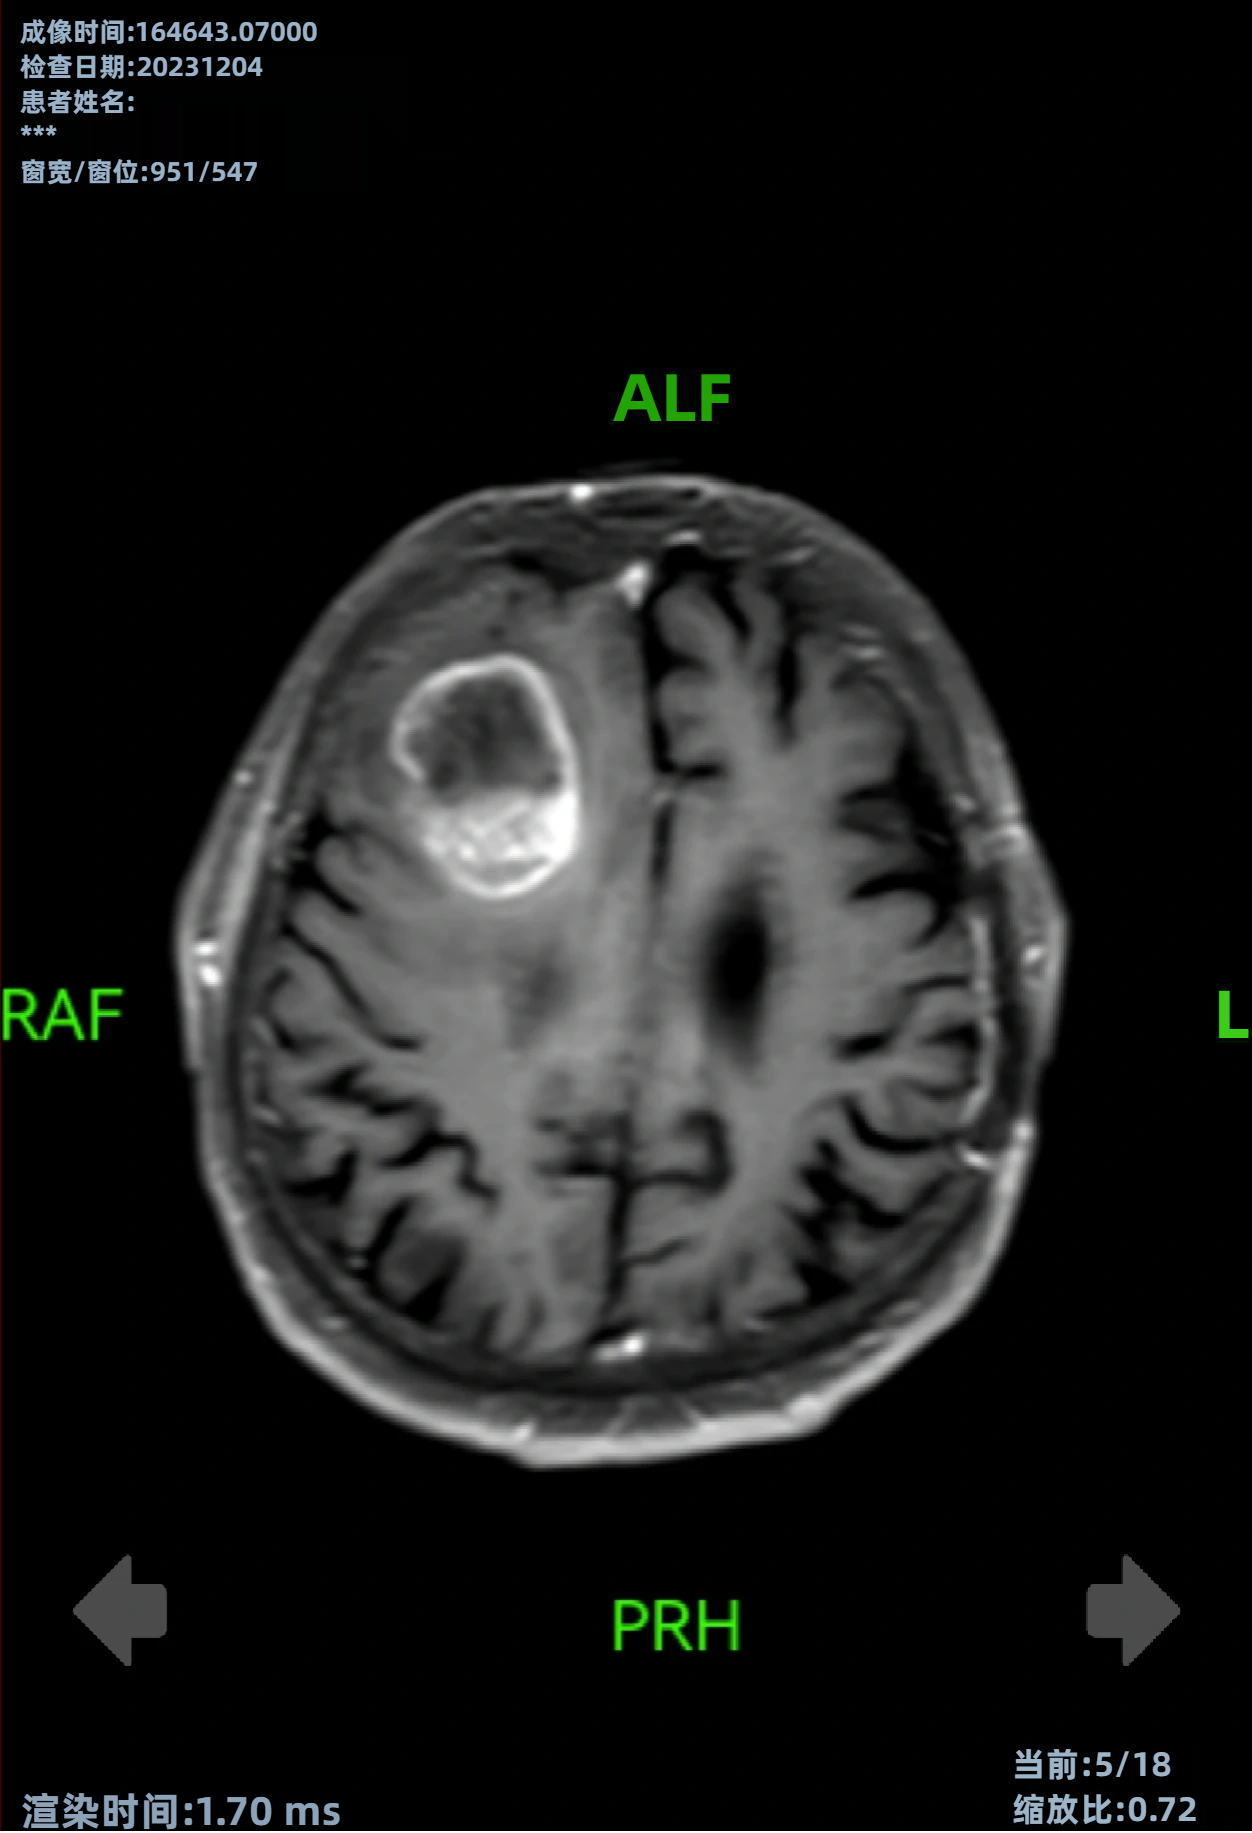

病史摘要:30岁男性患者,有大量饮酒史,无吸烟及非法药物使用史,否认胃肠道恶性肿瘤等家族史。因精神状态改变被送至急诊科。 诊疗过程:初始检查发现中度转氨酶升高,尿毒物筛查大麻素阳性,多种病毒血清学阴性。影像学检查发现孤立性左肾、输尿管结石伴急性肾损伤及腹腔肿块等。肿瘤标志物大多正常,LDH升高等。CT引导下活检,病理及免疫组化有相应表现。初步诊断为起源于胰腺的异位肝细胞癌伴广泛转移,先接受